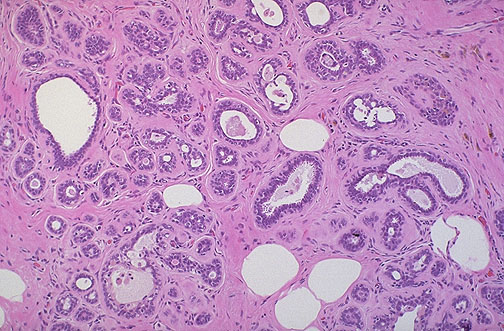

Prominent sclerosing adenosis, one of the features of fibrocystic changes, is demonstrated here by the appearance of a proliferation of small ducts in a fibrous stroma. Although it is benign, the gross and mammographic appearance may mimic carcinoma, and it can be difficult to distinguish florid sclerosing adenosis from carcinoma on frozen section. |